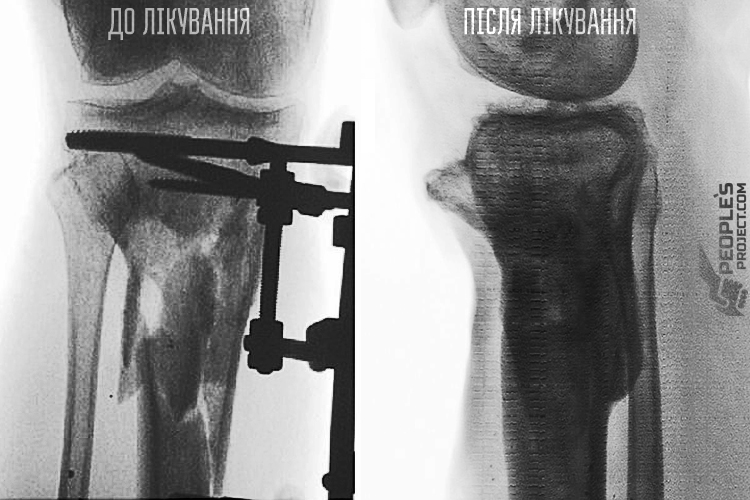

До клініки Іван впевнено прийшов на власних двох. Власне вже це перемога: адже до проекту хлопець надійшов із потрощеною гомілкою. І обстеження, і рентгенівські знімки показали: кістка чудово зрослася і набула анатомічної форми. Власне сьогодні ніщо не заважає Іванові користуватися ногою у повну силу.

Іван трохи подумав, та й долучився до проекту «Біотех-реабілітація поранених» – саме клітинні технології стали останньою надією бійця. На лікування хлопця ми, волонтери People’s Project, зібрали майже 350 тисяч гривень народних пожертв. У ході кількох операцій кісткові уламки зібрали докупи і заповнили місце ураження клітинами самого пацієнта. З часом клітинні матеріали зробили свою справу і перетворили сукупність осколків у цілу кістку первинної міцності. Певний час реабілітації, милиці, паличка а потім і самостійно – і Іван знову пішов на власних ногах.